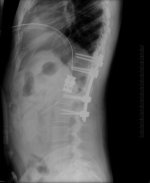

I broke my spine, had two surgeries (T12 arthrodesis), had to relearn how to walk again because I couldn't move my legs after the crash...